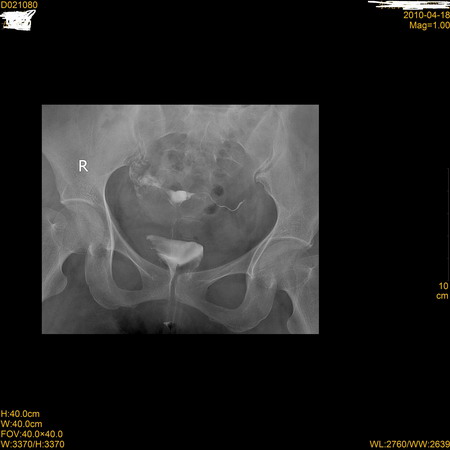

标题: X7194:右侧输卵管是怎么解释

右侧输卵管子宫部(原称角部)闭塞伴周围逆流。左侧输卵峡部闭塞。

右侧输卵管子宫部闭塞伴周围逆流。左侧输卵峡部闭塞可能。

右侧输卵管子宫部闭塞伴周围逆流,有可能是导管堵塞(第2、3张图片对比)